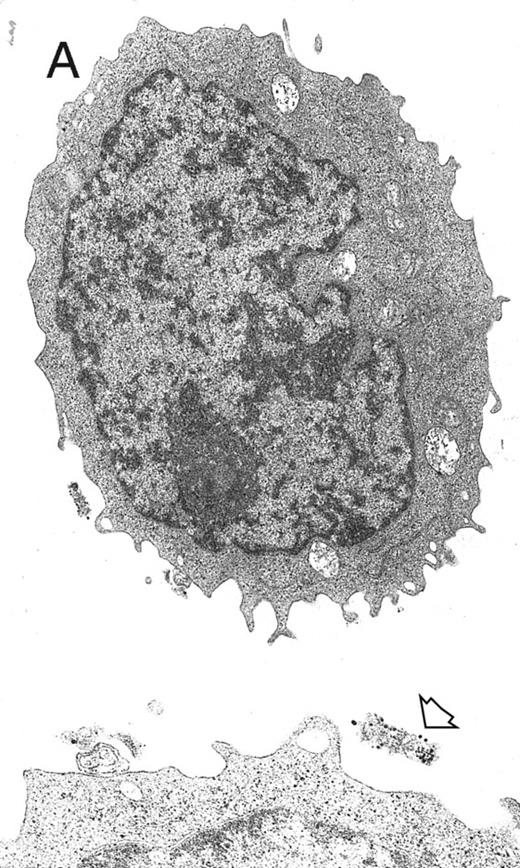

A well-differentiated megakaryocyte (original magnification × 3,080) generated from purified CD34+ cells cultured for 12 days in the presence of MIP-1α, IL-3, IL-6, IL-11, FL, SCF, and MGDF. A normal distribution of granules, mitochondria, and other cytoplasmic organelles is visible.